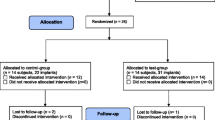

The study design was a single-blind, randomized, controlled, ex vivo investigation with intra-subject control. Study participants were 20 consecutive patients with at least 4 hopeless implants, in function for >12 months and with progressive bone loss exceeding 50%, which had to be explanted. Implants of each patient were randomly assigned to the untreated control group or one of the three decontamination procedures: mechanical debridement with air-powder abrasion, chemical decontamination with hydrogen peroxide and chlorhexidine gluconate, or combined mechanical-chemical decontamination. Following surgical exposure, implants selected as control were retrieved, and afterwards, test implants were decontaminated according to allocation and carefully explanted with a removal kit. Microbiological analysis was expressed in colony-forming-units (CFU/ml).

The study was designed as a single-blind, randomized, controlled, ex vivo investigation with intra-subject control to compare the semiquantitative concentrations of colony-forming units (CFU/ml) and to assess the qualitative microbial composition on the surface of retrieved infected implants clinically treated with three different decontamination methods.

Randomization

Before the start of the study, selected implants of each patient were randomly assigned to one of the four groups (untreated control, mechanical debridement, chemical decontamination, mechanical debridement combined with chemical decontamination) using a list of random numbers generated using CLINSTAT software (Martin Bland, York, UK) and sequentially numbered opaque sealed envelopes. The envelopes were opened by the surgeon, and the assigned decontamination method was carried out. The microbiologist assessor was unaware of the delivered treatment. The treatment code was not revealed until all microbiological tests had been completed, and the data file had been established.

Twenty consecutive patients (11 males and 9 females; age 65.75 ± 9.67 years) aged > 18 years were selected for a total of 80 implants with different rough surfaces (4 for each subject). No test or control implants were lost during decontamination procedures or the incubation period. In all groups, no intraoperative complications occurred (e.g., emphysema formation) and the postoperative wound healing was uneventful.